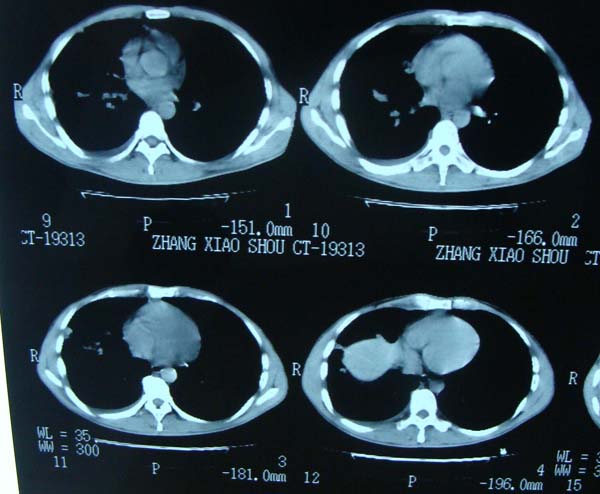

标题: CT15132:男,26岁。建筑混凝土工人。发热。咳。 [打印本页]

标题: CT15132:男,26岁。建筑混凝土工人。发热。咳。

右肺继发型肺结核,右侧胸腔积液、胸膜肥厚粘连。

右肺继发型肺结核,右侧胸腔积液。

继发结核并胸水

胸膜肥厚

右肺及胸胸膜多个结节多考虑转移瘤,右侧胸水,结核次之。

右肺继发型肺结核,右侧少量胸腔积液、胸膜肥厚。